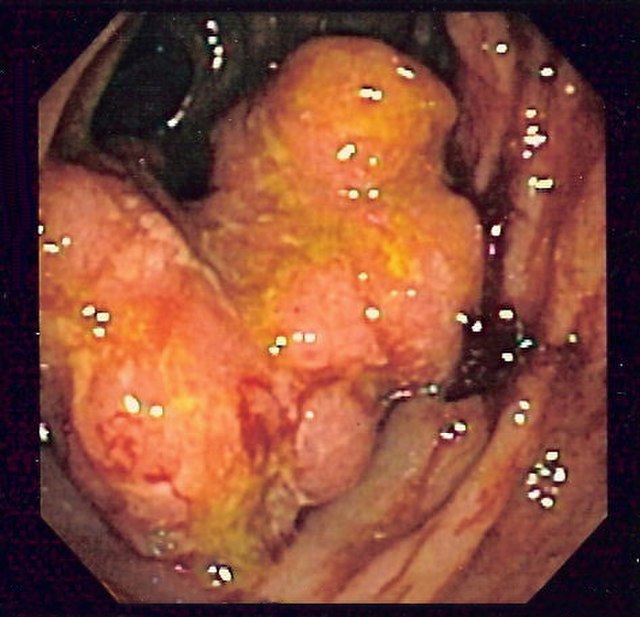

Sometimes the tumours grow deep inside the body. If there is plenty of room for them to grow before they cause symptoms, they can easily become very big and have formed many metastases before the person affected becomes aware of the problem. Lung cancers, stomach cancers and bowel cancers are rather like this.

Intra Camera

There are a number of different approaches to treating cancer. Some have been used for many years, whilst others involve cutting edge biotechnology. The choice of treatment will depend on the type and stage of the cancer. The ideal treatment attacks and destroys the tumour cells but leaves the healthy cells of the patient intact. No-one has yet found the perfect molecule, but we have an ever-expanding range of treatments to use against cancers.